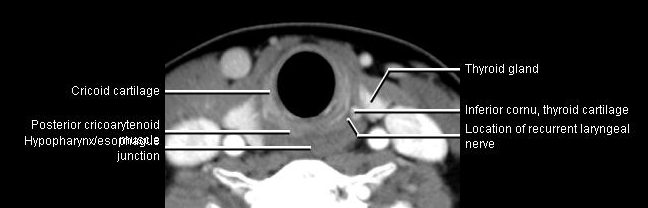

Phonation and dysphagia involve multiple coordinated structures in the larynx and pharynx. Radiation induced dysphagis appears to be related to dose to the phyaryngeal constrictor muscles and specific regions of the supraglottic and glottin larynyx.

Speech is impacted by doses to the epiglottis, base of tongue, aryepiglottic folds, false vocal cords upper esophageal sphincter and cricoid cartilage.

The mean laryngeal volume receiving > 50 Gy was a predictor of laryngeal edema. Vocal functions are usually well preserved with doses of 60 - 66 Gy. Dornfeld found a strong correlation between speech quality and dose to the ariepiglottic folds, pre-epiglottic space, false vocal cords and lateral pharyngeal walls at the level of the false vocal cords. A steep decrease in dose function was noted when doses exceeded 66 Gy.